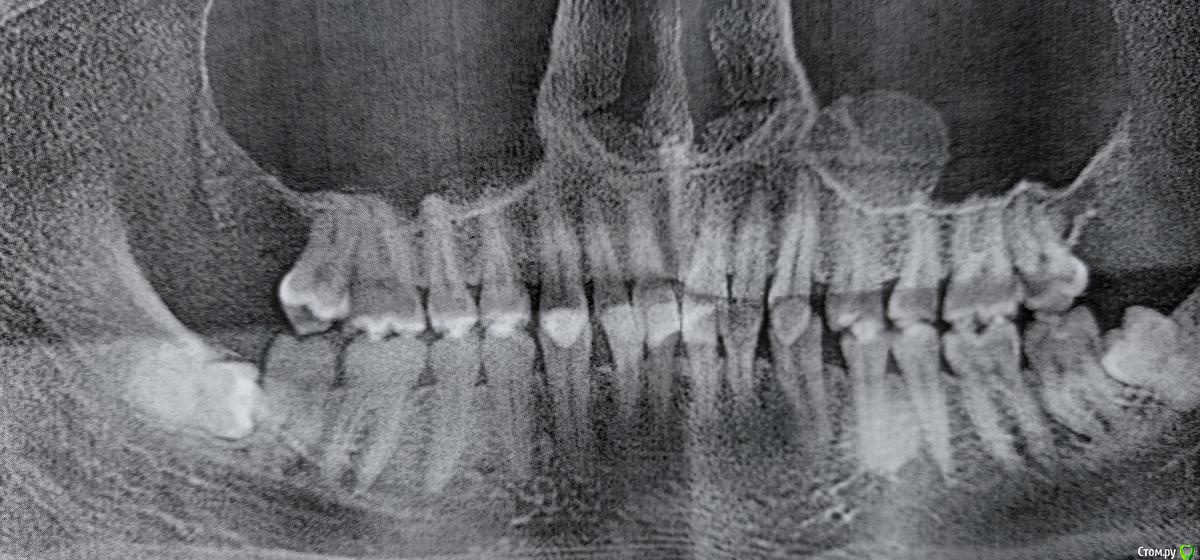

notarius Опубликовано 20 сентября, 2020 Поделиться Опубликовано 20 сентября, 2020 Здравствуйтевчера сделал КТ челюстиобнаружил лежачий зуб мудрости (сильно давит на семерку и болит тройничный нерв) предложили под общий наркоз резать костную ткань и удалять зуб мудрости или удалить семерку, в дальнейшем через время и зуб мудрости или съездить на консультацию и возможно удалить пьезо-ножом (ультразвук) ребята, пожалуйста, кто сталкивался, подскажите Ссылка на комментарий